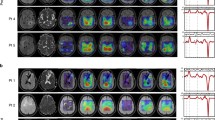

In vivo detection of BTK inhibition-mediated decreases in lactate, alanine, and total choline concentrations by noninvasive 1H MRS and correlation with MCL tumor growth

We established an MCL xenotransplant mouse model suitable for the noninvasive study of lymphoma tumors by 1H-MRS imaging (Fig. 4), mimicking the peripheral lymphadenopathy observed in lymphoma patients. As shown in Fig. 5a, the intra-tumoral concentrations of the three index metabolites, in particular lactate and alanine, profoundly decreased in response to IBR therapy in the highly sensitive MCL-RL cells, recapitulating the in vitro results obtained with these cells (Fig. 3b). Notably, an associated decrease in the MCL-RL tumor volume was observed in response to IBR (Fig. 5a). A comprehensive analysis of the moderately sensitive REC-1 xenografts yielded similar results (Fig. 5b), demonstrating highly significant IBR-mediated inhibition of intratumoral lactate and alanine concentrations associated with the inhibition of tumor growth. In comparison, JeKo-1 tumors with low sensitivity to BTK inhibition yielded qualitatively similar results, although the changes in lactate, alanine, and tumor growth inhibition were much less robust and less statistically significant (Fig. 5c). The total choline concentration did not change noticeably in either REC-1 or JeKo-1 tumors (Fig. 5b and c, supporting the notion that lactate and alanine, rather than total choline, emerge as more universal biomarkers of BTK inhibition. Finally, resistant MCL-SL tumors displayed no detectable IBR-mediated inhibition of any of the metabolites or tumor growth (Fig. 5d). The effect of BTK inhibition on tumor growth was confirmed by immunostaining of resected tumors from IBR-treated vs. drug vehicle-treated mice for cell proliferation-associated Ki-67 protein (Fig. S11). Accordingly, the staining indicated a significant drug-induced decrease in the tumor cell proliferation (Fig. S11).

Representative in vitro and in vivo 1H MR spectrum. a Representative High-Resolution 1H MRS of MCL cell extract measured at 9.4 T vertical bore Varian magnet. b Representative 1H MRS of subcutaneous MCL xenograft measured at 9.4 T horizontal bore Bruker console using STEAM pulse sequence. c Representative 1H MRS of subcutaneous MCL xenograft measured at 9.4 T horizontal bore Bruker console using1H MRS with Hadamard Selective Multiple Quantum Coherence pulse sequence. d Representation of animal preparation for in vivo 1H MRS

In vivo 1H MRS-detectable biomarkers of BTK inhibition-mediated suppression of tumor growth. The spectral peak area of lactate, alanine and choline signals normalized to the water signal measured by 1H MRS with Hadamard Selective Multiple Quantum Coherence (Had-Sel-MQC) transfer and stimulated echo acquisition mode (STEAM) pulse sequences, respectively, and tumor volume using calipers after treatment with IBR measured at Day 0, Day 2, and Day 7 in a MCL-RL (n = 5), b REC-1 (n = 5), c JeKo-1 (n = 5) and d MCL-SL (n = 5). IBR was given with the dose of 256 mg/kg, orally, once daily each day, thereafter. We have included drug vehicle treated controls in each MCL PDXs except MCL-RL. We have included drug vehicle treated controls in each of the four MCL xenotransplant models. The values are presented as the mean ± SEM, with the p-value of the difference between BTK inhibitor-treated vs. controls also depicted